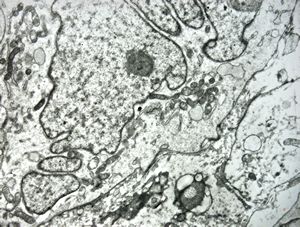

F,40y. | myopathy - mild steatosis

F,46y. | myopathy - steatosis

M,61y. | myopathy - steatosis